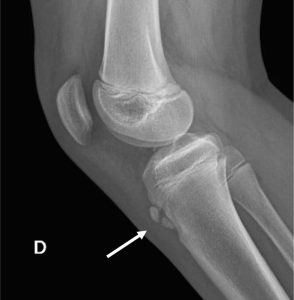

Su diagnóstico es fundamentalmente clínico (1) (27), requiere conocimientos de la anatomía de la rodilla, de los mecanismos de lesión, habilidad para el examen físico y conocimiento de los diagnósticos diferenciales. Aunque se deben solicitar estudios radiológicos en determinados cuadros atípicos para así descartar otras patologías. Destacan como hallazgos radiológicos en EOS: (24-25)

| Partes blandas | Hueso |

| Edema generalizado | Condensación, fragmentación, reestructuración. |

| Borrado de la grasa infrarotuliana | Osificación tibial irregular |

| Engrosamiento del tendón rotuliano | Aparición de osículos independientes |

| Ensanchamiento óseo | |

| Imagen en gota de cera de la epífisis tibial superior |